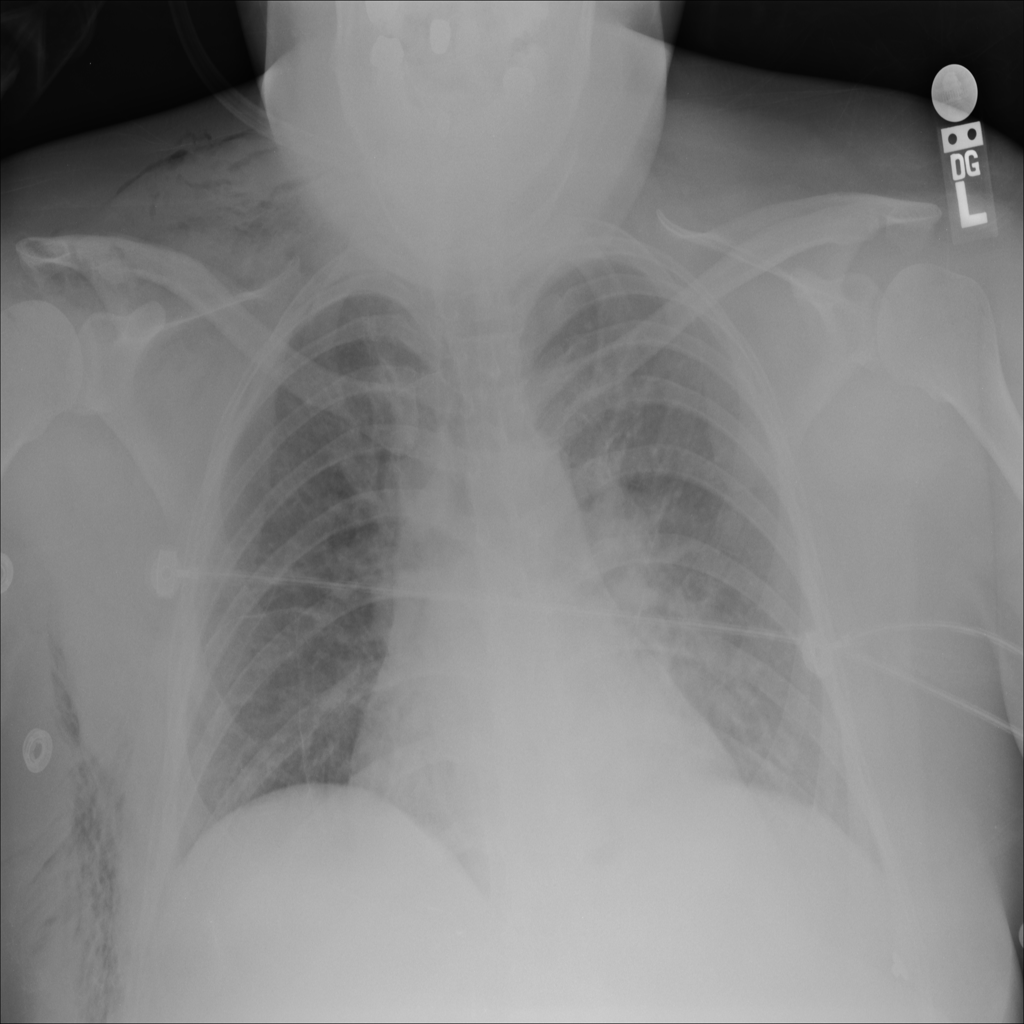

Showing up to 90 reference images for Emphysema.

PAT-894B · IMG-000Emphysema

PAT-894B · IMG-000

PA